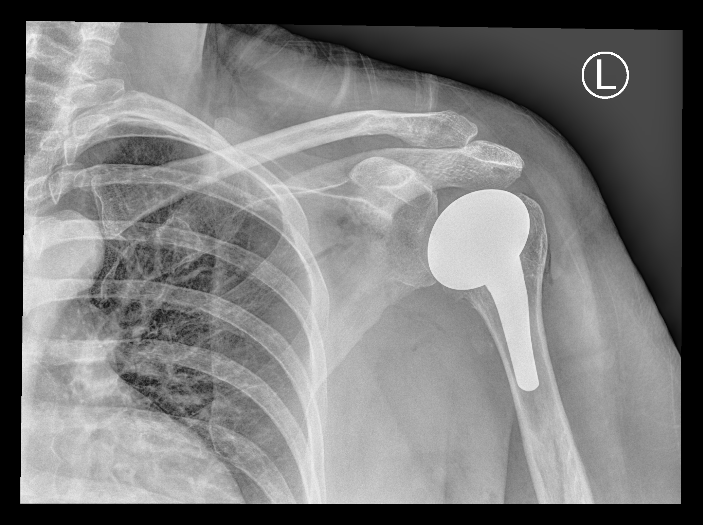

Um… hi? I hope you’re still around, and doing okay out there? I seem to be back. Perhaps older and a touch more silver. Definitely more metal than previously. I ended up with avascular necrosis in an old fracture (what is it with me and avascular necrosis?!!) and had my shoulder replaced last July. Yes, that’s my x-ray, not a stock image. Yes, it was a painful surgery to undergo! And no, I’m still not allowed to lift more than 2kg with my left arm (and guess who is left-handed, because of course I am).